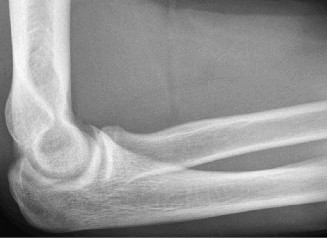

On examination, he has tenderness to palpation over his olecranon and pain with terminal elbow extension. He has no evidence of varus or valgus instability. No pain with resisted wrist flexion. His images are shown (Figs. 2–108 to 2–110).

Figure 2–109

Figure 2–110